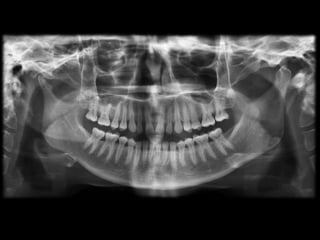

Ankylosis treated with total joint prosthesis

Panoramic view shows prosthesis (arrow), consisting of artificial fossa (fixed with six

titanium screws in temporal bone), and artificial condylar process (fixed with seven titanium

screws to mandibular ramus